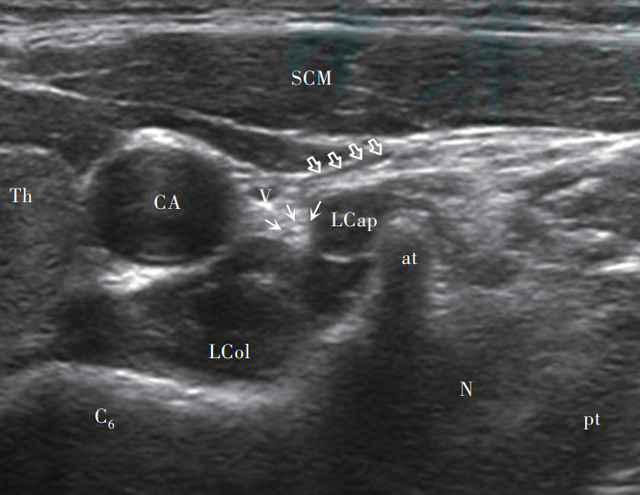

超声引导下星状神经节阻滞图

对于急慢性失眠和希望减停安眠药物的市民朋友们,可和周阿姨一样采用星状神经节阻滞术将极少量局麻药或者合用一些神经营养药物注入交感神经,解除过度紧张及功能亢进状态,从而改善睡眠,并实现快速舒适减停药。

【超声引导下星状神经节阻滞术】

星状神经节阻滞疗法中国专家共识(2022版)推荐用于失眠治疗,可有效降低交感神经兴奋度,显著改善睡眠。